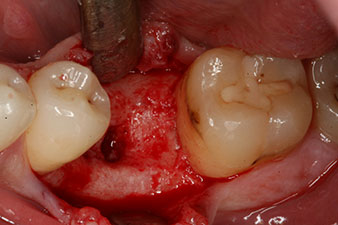

Въртящият момент, използван за машинно-задвижвано поставяне, е 43 Ncm. Освен това, след завинтване на измервателния щифт (SmartPeg), специално пригоден за импланта, стойността на ISQ се измерва със сондата на W&H Osstell ISQ модула.

Този модул е допълнителна екстра към Implantmed на W&H и е закачен към имплантологичния мотор (виж фиг. 11). Липсата на ISQ стойност непосредствено след поставянето е 64 оровестибуларно и 68 мезиодистално (максимална стойност = 100).

Тези стойности могат да показват отворено лечение или дори имедиатно възстановяване. Поради недостатъчния обем на кресталната кост при импланта, областта е подсилена с костните частици, събрани по време на препарацията на имплантното ложе и зашити, за да се изолира слюнката.